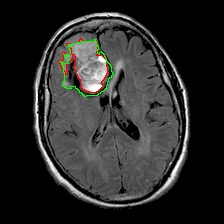

Neural processes have recently emerged as a class of powerful neural latent variable models that combine the strengths of neural networks and stochastic processes. As they can encode contextual data in the network's function space, they offer a new way to model task relatedness in multi-task learning. To study its potential, we develop multi-task neural processes, a new variant of neural processes for multi-task learning. In particular, we propose to explore transferable knowledge from related tasks in the function space to provide inductive bias for improving each individual task. To do so, we derive the function priors in a hierarchical Bayesian inference framework, which enables each task to incorporate the shared knowledge provided by related tasks into its context of the prediction function. Our multi-task neural processes methodologically expand the scope of vanilla neural processes and provide a new way of exploring task relatedness in function spaces for multi-task learning. The proposed multi-task neural processes are capable of learning multiple tasks with limited labeled data and in the presence of domain shift. We perform extensive experimental evaluations on several benchmarks for the multi-task regression and classification tasks. The results demonstrate the effectiveness of multi-task neural processes in transferring useful knowledge among tasks for multi-task learning and superior performance in multi-task classification and brain image segmentation.